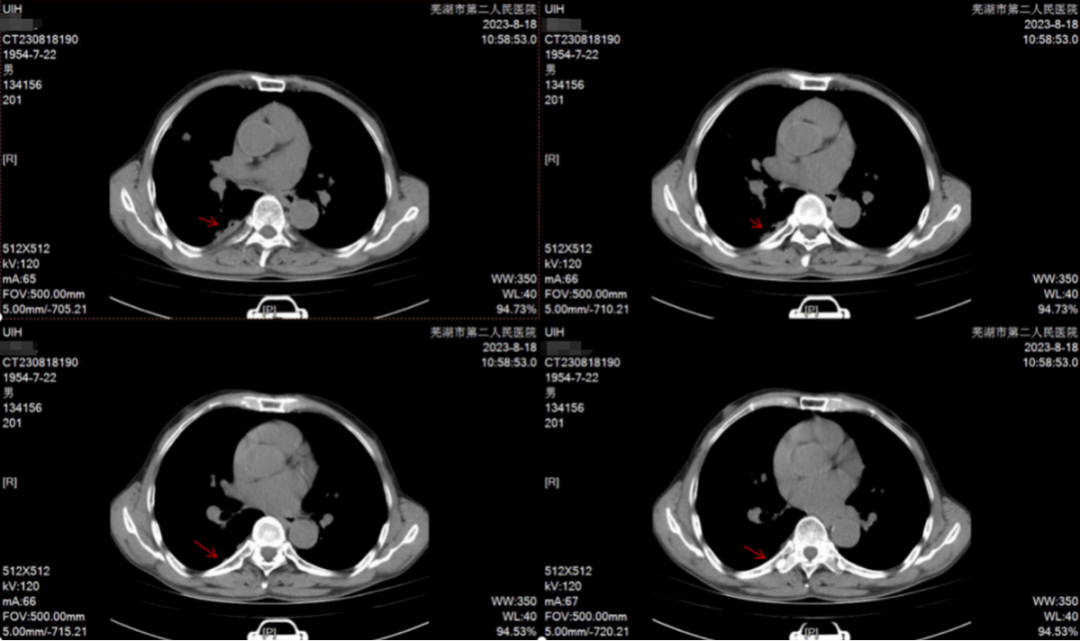

2023-08-18胸部CT:8周期病灶稳定。

影像学检查结果图